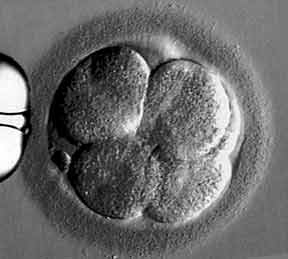

Hundefötus 55 Tage alt

Quelle: National Geographic

Welpe kurz vor der Geburt

Quelle: National Geographic